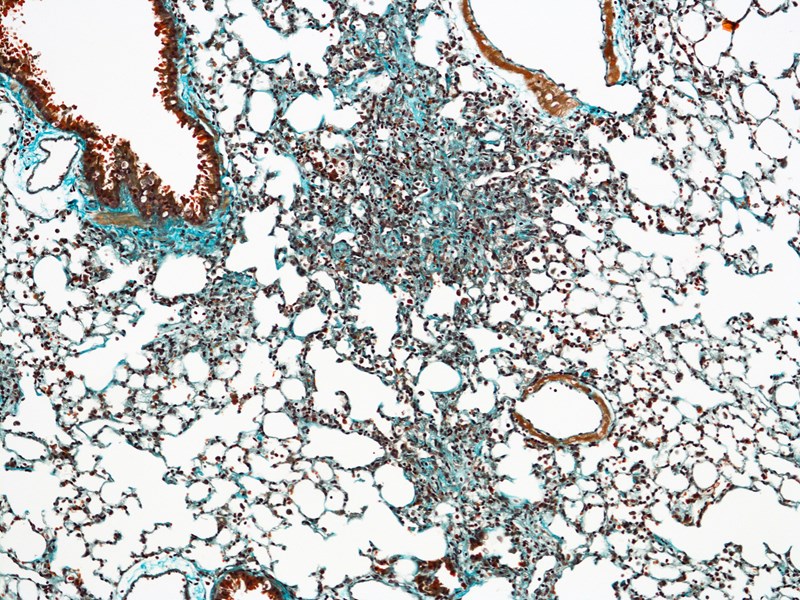

Lung Disease

Lung fibrosis is caused by more than 100 different types of lung disease and affects millions of people worldwide.

Idiopathic pulmonary fibrosis (IPF) is a specific and aggressive form of lung disease that has no cure and a similar life expectancy as lung cancer (20% survival over 5-years).